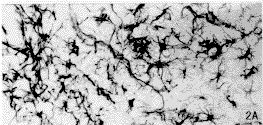

Nissl染色切片可见切口损伤的范围包括皮质、扣带和胼胝体等。术后14 d,损伤侧皮质的Nestin阳性反应最明显,涉及的范围较广。切口周围的Nestin免疫染色呈现一个梯度反应模式。离伤口越近处,反应越强烈,Nestin阳性细胞数越多;离伤口越远处,反应越弱,Nestin阳性细胞越少。皮质浅层的反应范围要比深层的大,冠状片上可观察到一个Nestin阳性的楔形反应区(图1A,见插页1)。而从前后的连续切片来看,随着逐渐远离伤口,Nestin阳性细胞的消失也逐渐是从皮质深层过渡到浅层(图1B,图1C)。在最靠近伤口的区域,Nestin阳性细胞密集,胞体肥大,多呈星形,突起粗大而长,互相交织成网,环绕着伤口的周边。离伤口稍远的部位,Nestin阳性细胞密度降低,胞体较小,突起较细而短(图2A)。非损伤侧的皮质未观察到Nestin的表达。GFAP免疫染色显示在伤口的周围出现许多胞体较大的星形阳性细胞,其出现的模式与Nestin阳性细胞的反应模式相似。但其涉及的范围、阳性细胞密度、胞体和突起的大小均小于Nestin阳性细胞(图2B)。术后30 d,皮质内切口周围仍存在大量的Nestin阳性细胞,但阳性细胞的排列较14 d的整齐(图3A)。而GFAP阳性的肥大细胞数目及其突起数目均较14 d的少(图3B)。

图2 损伤后14 d大脑皮质的Nestin阳性细胞汕(A)和GFAP阳性细胞(B)。左侧近切口处:右侧远离切口处。 x200

Flg. 2 The Nestin postive cells(A)and GFAP positive cells(B) in the cortex in the l4 day after injury。 The left side is near the cut. The right side is far from the cut. x 200